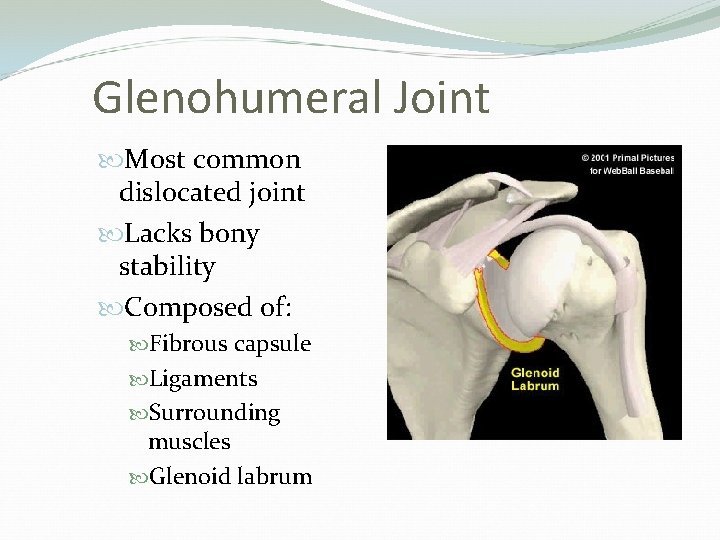

Glenohumeral Joint Most common dislocated joint Lacks bony stability Composed of: Fibrous capsule Ligaments Surrounding muscles Glenoid labrum